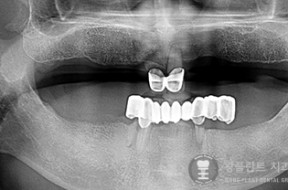

전후사례